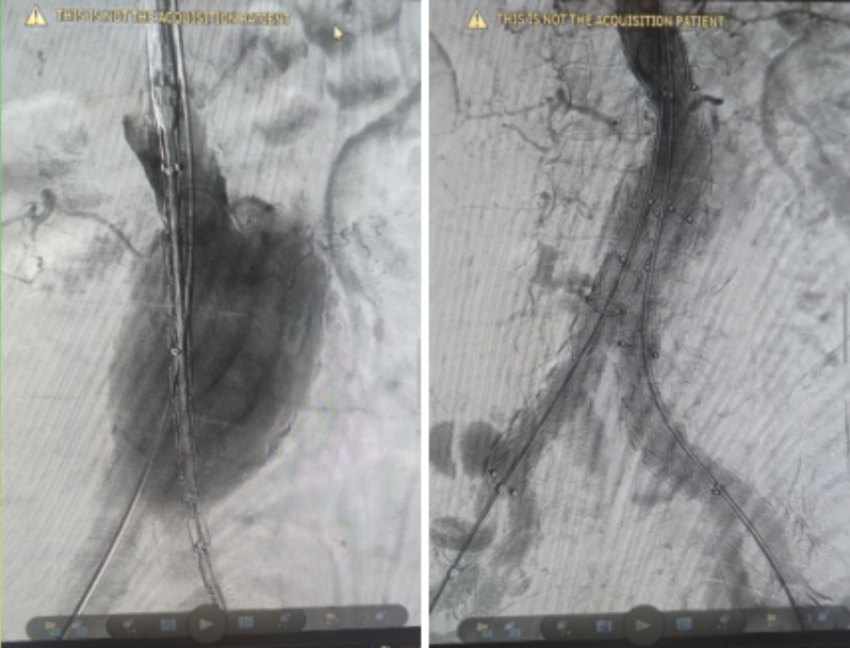

Волгоградская областная клиническая больница №1 вновь продемонстрировала высочайший класс медицины, успешно проведя сложнейшую операцию по спасению пациента с жизнеугрожающей аневризмой брюшной аорты. Уникальное эндоваскулярное вмешательство с использованием стент-графта открывает новую эру в лечении сосудистых патологий региона.

Пациент, пожилой мужчина старше 70 лет, столкнулся с серьезнейшей угрозой – аневризмой брюшной аорты огромного размера. Состояние осложнялось симптомами сдавления соседних органов, что требовало незамедлительного вмешательства. Однако, учитывая возраст больного и наличие у него множества тяжелых хронических заболеваний, традиционная открытая операция несла в себе неприемлемо высокий риск. Именно поэтому команда высококвалифицированных сосудистых хирургов Волгоградской ОКБ №1 приняла смелое решение о проведении передовой малотравматичной операции.

Основной задачей операции было предотвращение катастрофического разрыва аневризмы, который в такой ситуации является смертельным. И современная медицина предложила элегантное решение.

Вся эта конструкция вводится в аневризму через крошечный прокол, как бы «зашивая» ее изнутри. Она создает новый, прочный и безопасный путь для кровотока, полностью исключая нагрузку на пораженный участок аорты. Таким образом, функция жизненно важного магистрального сосуда восстанавливается, а угроза разрыва и опасных осложнений устраняется.